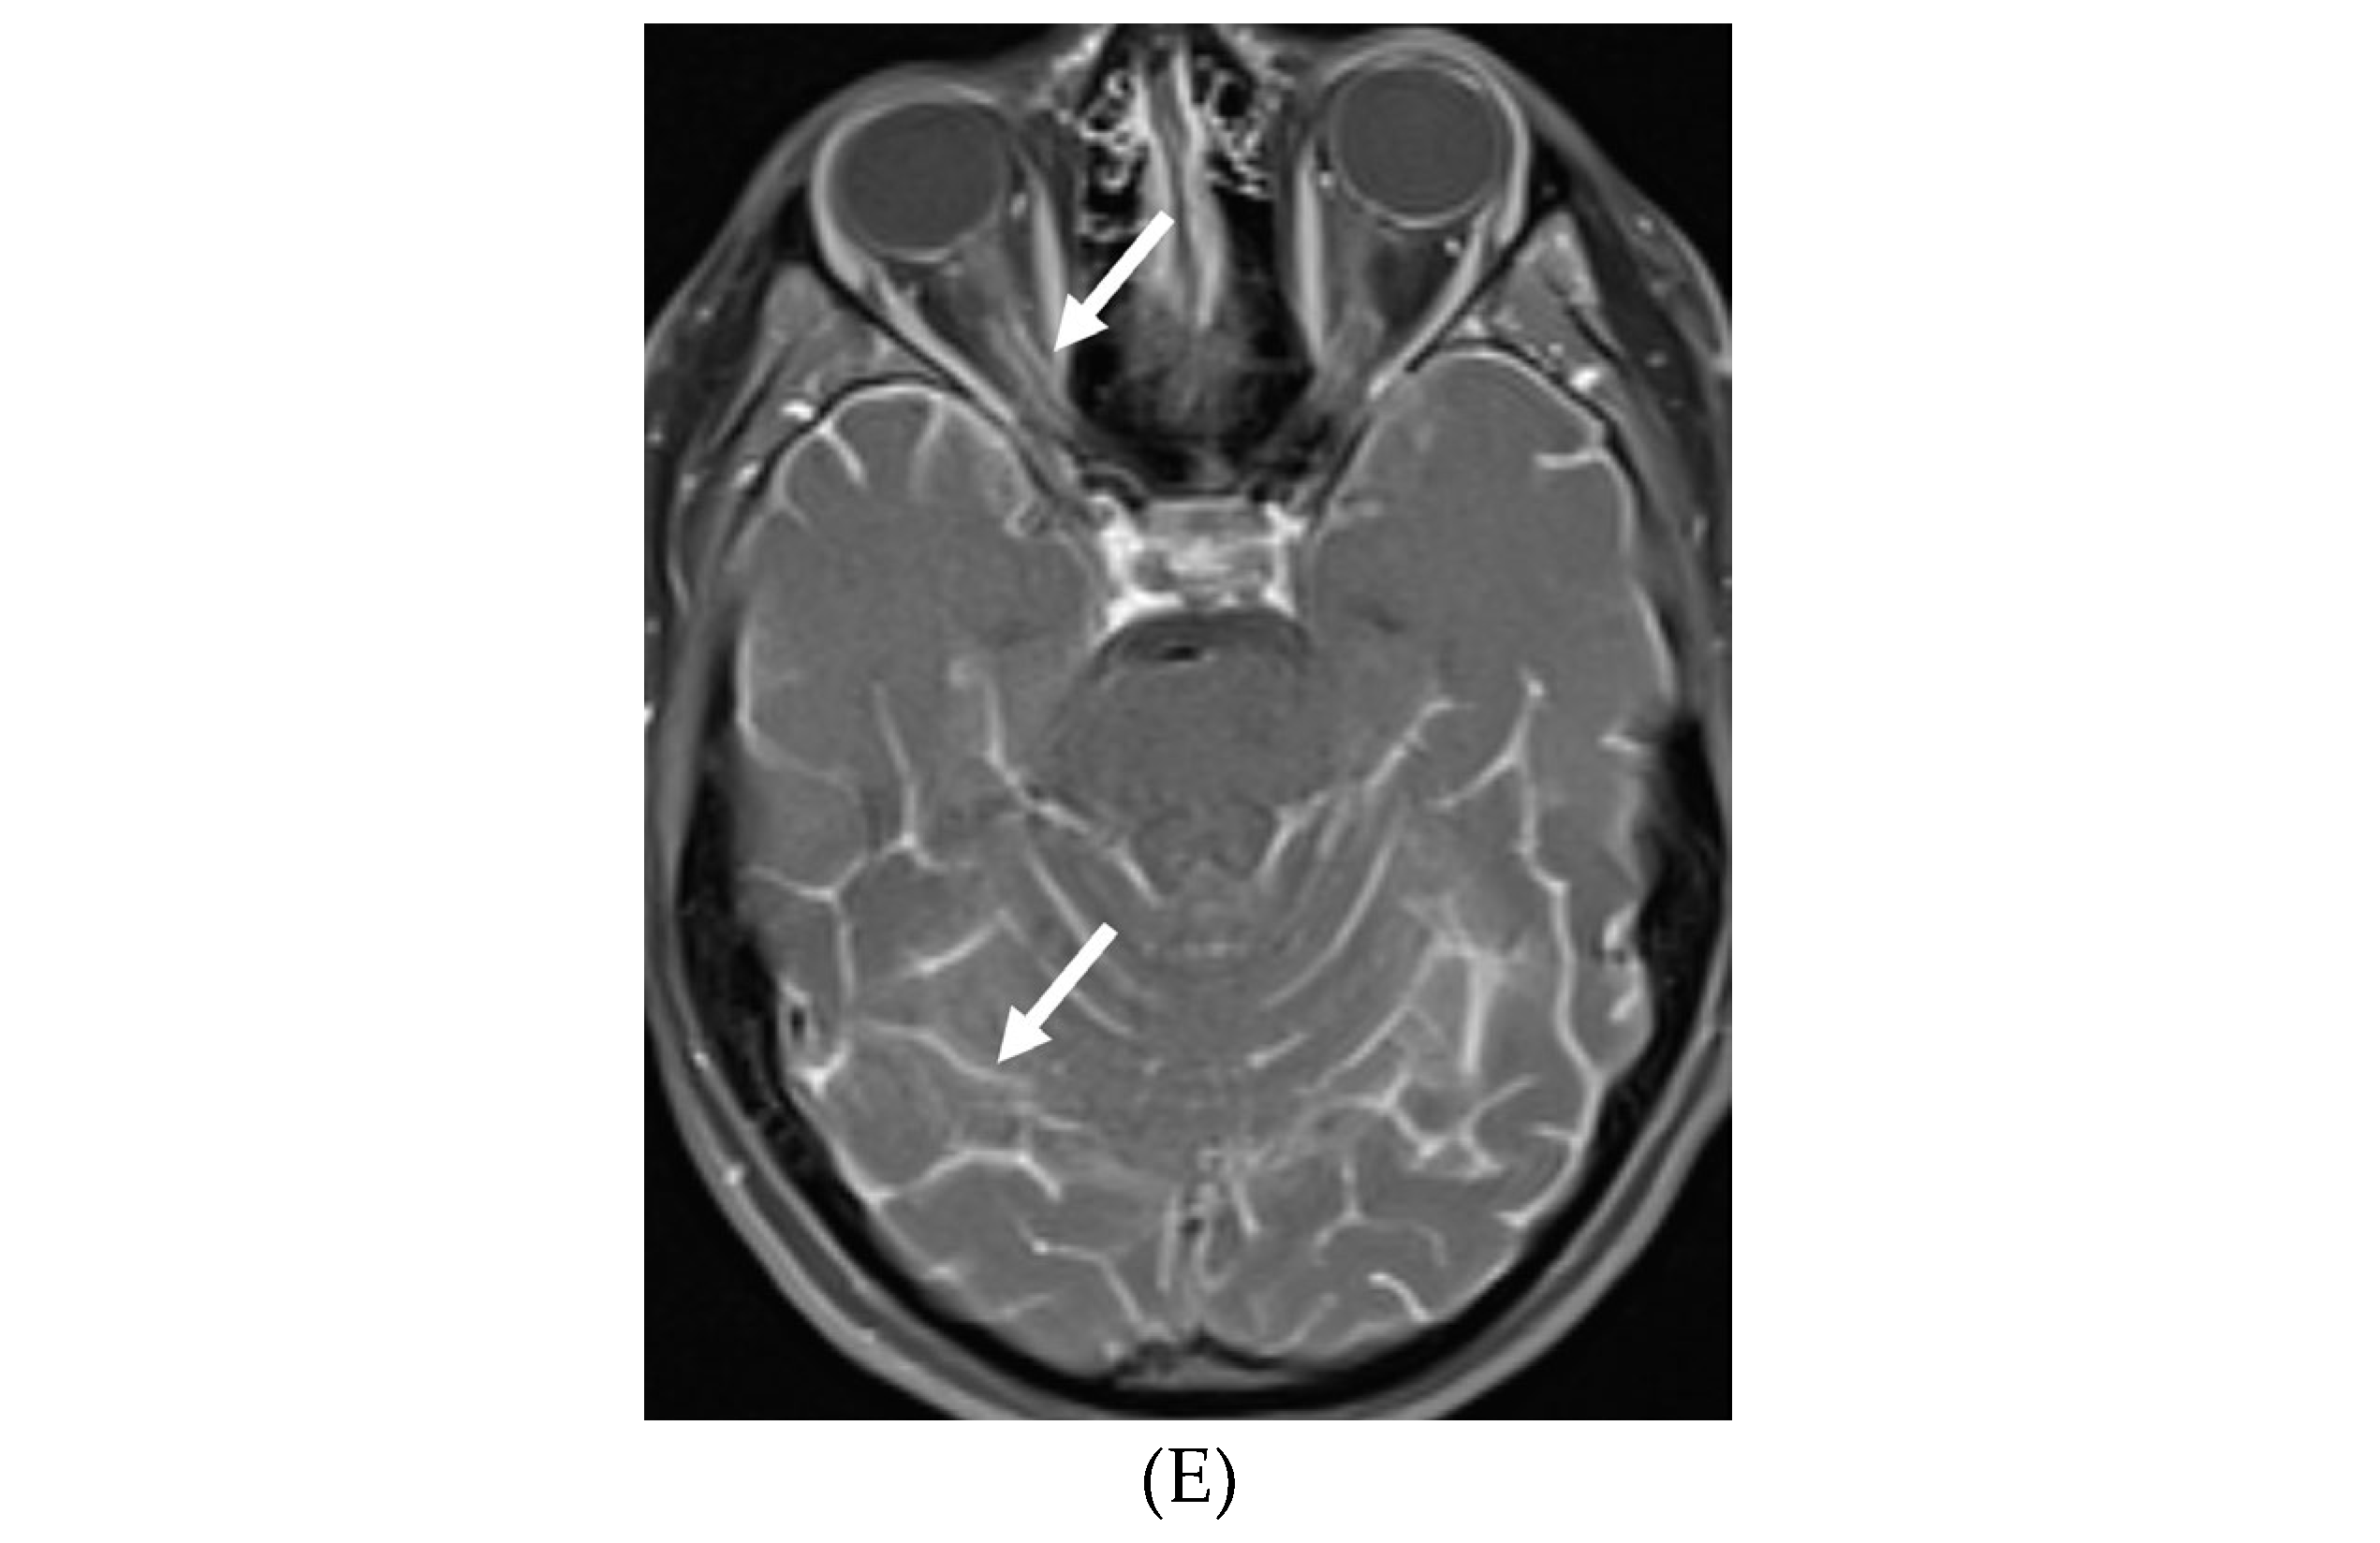

MOYA MOYA